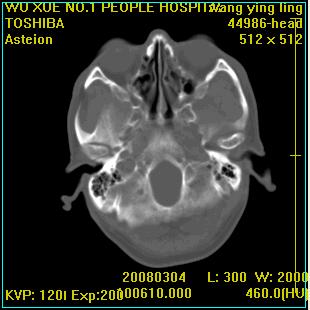

标题: CT12023:女,50岁,头部包块二月,伴轻微头痛,不伴发热。 [打印本页]

标题: CT12023:女,50岁,头部包块二月,伴轻微头痛,不伴发热。

这种病例还是比较多见,起源于颅骨板障,向颅内和颅外生长,考虑血管瘤或嗜酸性肉芽肿,要是有增强ct就好了。

多发溶骨性破坏,骨嗜酸性肉芽肿可能,转移瘤待排除,建议进一步检查。

破坏区边界较清楚,还是考虑良性病变---嗜酸性肉芽肿可能。

病灶呈溶骨性骨破坏,考虑嗜酸性肉芽肿可能转移瘤不除外建议追查病史并进一步检查